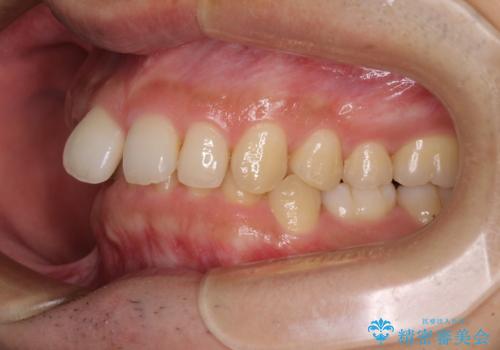

右上と左下は永久歯が欠如しており、大きさの大きく異なる乳歯が残存していたため、奥歯の咬み合わせを構築するために苦労しました。

元々隙間の空いていた上顎の正中は、後戻りのリスクが高いため、下顎前歯同様ワイヤー固定を行いました。